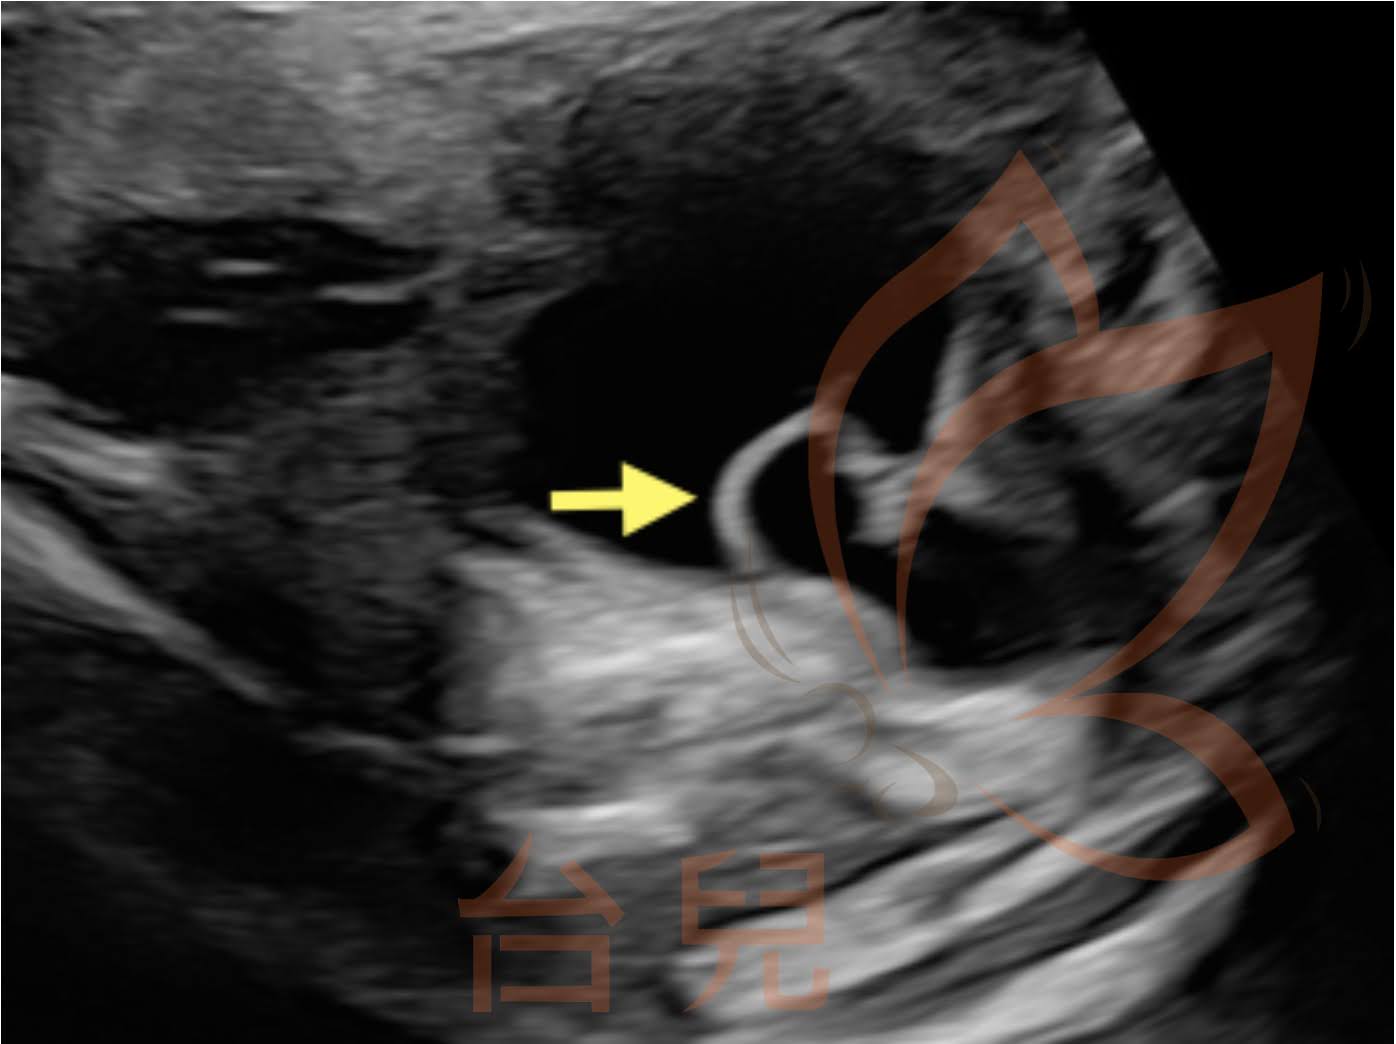

第一個案例來診時懷疑為多囊腎,在不同角度下檢查才發現腫脹的水泡狀構造其實是腎盞,還有一條水腫的輸尿管由嚴重腫脹的腎盂連至膀胱(圖一),說明了多角度檢查的重要性。另一個案例於產後確診為雙套腎,且輸尿管囊腫時有外翻(圖二)。

與會的馬偕小兒腎臟科蔡政道醫師提醒我們,輸尿管囊腫與雙套腎關聯性很高,連接上面那套集尿系統(upper moiety)的輸尿管特別容易合併輸尿管囊腫,另一套集尿系統(lower moiety)則較容易發生腎盂輸尿管交接處阻塞(ureteropelvic junction obstruction, UPJO)。因此,輸尿管囊腫的個案需要回頭仔細檢查腎盂;雙套腎的個案在後續追蹤時也最好多注意膀胱,觀察是否出現輸尿管囊腫。